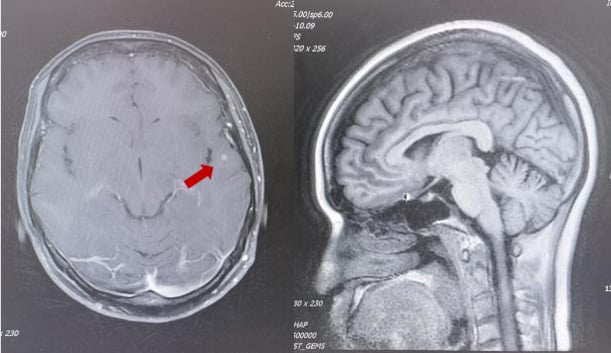

2025年2月,患者再次出现疾病进展,头颅MR显示左侧额顶叶异常强化软组织肿物,伴周围脑组织水肿,考虑脑转移。胸腹部CT显示肝脏病灶增大。

面对脑转移的再次出现,MDT团队决定启用新一代ADC药物——T-DXd(德曲妥珠单抗)。德曲妥珠单抗是目前HER2阳性乳腺癌治疗领域的一颗“新星”,它具有更高的药物抗体比(DAR),即每个抗体携带更多的化疗药物分子,同时具有“旁观者效应”,可以杀死周围未表达HER2的癌细胞。这使得它在治疗HER2低表达和脑转移方面展现出卓越的疗效。

患者接受了11周期的德曲妥珠单抗治疗。仅仅2周期后,患者右下肢无力症状明显好转;4周期后,右下肢肌力恢复,ECOG评分达到0分(意味着完全正常活动)。治疗过程中,骨髓抑制I-II度,胃肠道反应I度,未见间质性肺炎等严重副作用。影像学复查显示,疗效评价为部分缓解(PR)。这再次证明了创新药物在多线治疗失败后,仍能为患者带来显著的生存获益和生活质量改善。

3. 脑转移的治疗策略:全身治疗优先